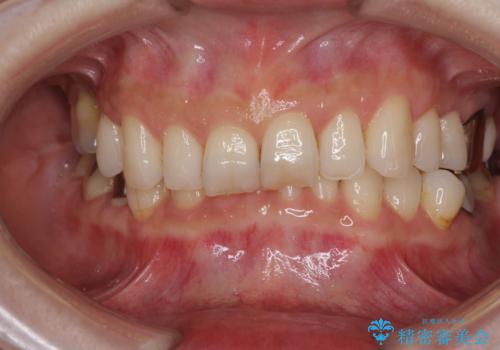

![[突き出た前歯を引っ込めたい] ワイヤー矯正とマウスピース矯正の併用治療の症例 治療前](https://seimitsushinbi.jp/wp/wp-content/uploads/2024/08/IMG_0066-500x350.jpg?v=1723179360)